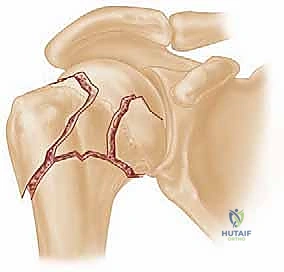

Insert an Acutrak 2, mini-Acutrak 2 screw (Acumed, Beaverton, OR), or other cannulated headless compression screw of appropriate length (at least 4 mm shorter than the measured scaphoid length) to within 1 to 2 mm of the distal surface. The tip of the screw should not penetrate the distal surface, and the proximal end of the screw should rest 2 mm deep to the proximal articular cartilage ( TECH FIG 2D,E). Confirm satisfactory screw position and fracture reduction with fluoroscopy. The screw should be inserted down the central axis of the scaphoid. If any doubt exists, use the arthroscopic portals to confirm that the screw is buried in the scaphoid. The 3-4 portal and the radial midcarpal portals provide the best view to ensure that the fracture is adequately reduced and that there is no violation of the midcarpal joint. ### Displaced Scaphoid Waist Fracture Insert two percutaneous 0.062-inch smooth Kirschner wires dorsally into each fragment perpendicular to the long axis of the scaphoid to be used as joysticks to reduce the fracture ( TECH FIG 3A,B). Position the wrist as previously described. The guidewire from the Acutrak 2 system (or the surgeon's chosen system) is inserted from proximal to distal, starting dorsally and aiming for the central axis of the distal fragment. The guidewire is driven through the distal fragment and out through the volar skin of the hand. The protruding tip is then pulled volarly until the wire is only in the distal fragment ( TECH FIG 3C).24, 25 115

### TECH FIG 2 • A-C. Before screw insertion, the position of the Kirschner wire must be changed from its position used for arthroscopy. The Kirschner wire should be driven from volar to dorsal until the distal end lies just beneath the articular surface of the scaphoid. D,E. Screw fixation of minimally displaced scaphoid fracture via the dorsal percutaneous technique. The screw tip should rest within 1 to 2 mm of the distal cortex. Excellent compression should be obtained with this technique. The proximal fragment, which is now freely mobile, is reduced manually using the Kirschner wire joysticks. Once the fracture is reduced, the central guidewire is driven from volar to dorsal into the proximal fragment, securing it in place ( TECH FIG 3D).24, 25 The guidewire is further advanced from volar to dorsal until its distal tip is just within the subchondral bone of the distal articular surface. This allows for measurement of the screw length as previously described.

### TECH FIG 3 • A. Reduction of a displaced scaphoid waist fracture using Kirschner wire joysticks. B. The Kirschner wire joystick technique for fracture reduction.